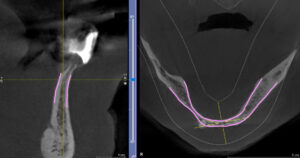

아 그리고, 이 분은 하악골의 뼈가 너무 좁아서 네비게이션 수술이 꼭 필요했던 분이었어요. 보통 하악골은 이렇게까지 얇은 분은 드물지만 이렇게 좁고 딱딱한 뼈에는 더 많은 주의를 기울여서 수술을 해야 합니다.

치료전후 CT 비교사진입니다. 겨우 뼈 속에 임플란트를 위치시켜서 완성한 모습이에요. 네비게이션이 도움이 된 수술입니다.